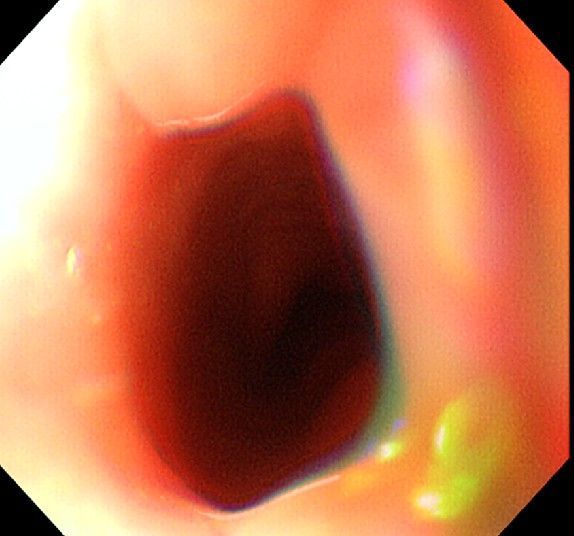

위 내시경을 찍었는데 위염 종류 사진을 알 수 있을까요? (사진 많습니다..)

한달 전 쯤에 소화불량과 속쓰림이 3개월 동안 약을 먹어도 낫지 않아 위 내시경을 찍었는데 위에 염증이 많이 있다는 이야기를 들었습니다...그런데 상태가 얼마나 안 좋은지 어떤 종류의 위염인지에 대해서는 물어봐도 안 알려주셔서 여기에라도 올려서 여쭈어봅니다... 제 상태가 얼마나 심각한 걸까요..

사진상으로 보아서는 정상에 가까운 점막상태이거나 약간의 표재성 위염이 있는 정도로 보입니다.

홍반성 위염이 있으며 경증의 역류성 식도염이 있습니다